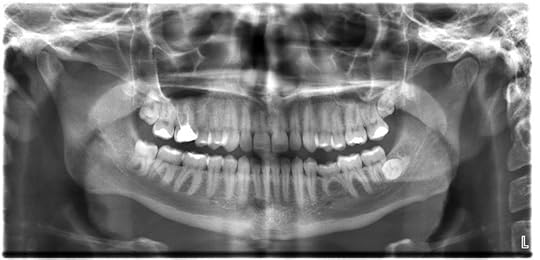

A rainbow above the mesas in Utah.Credit: David Parker/ Science Photo Library http://lightexhibit.org/bio_image8.ht... am: A trip to the dentist brings X-rays. Because it is one of the most energetic forms of light, X-rays can penetrate muscle and tissue, casting shadows on detectors of denser bone and teeth.

Dental X-rays.Credit: Dmitry G12:00 pm: Checking your email, data streams over fiber optic cables, which are made of strands of glass or plastic that carry emails, videos, photos and more in the form of infrared light.